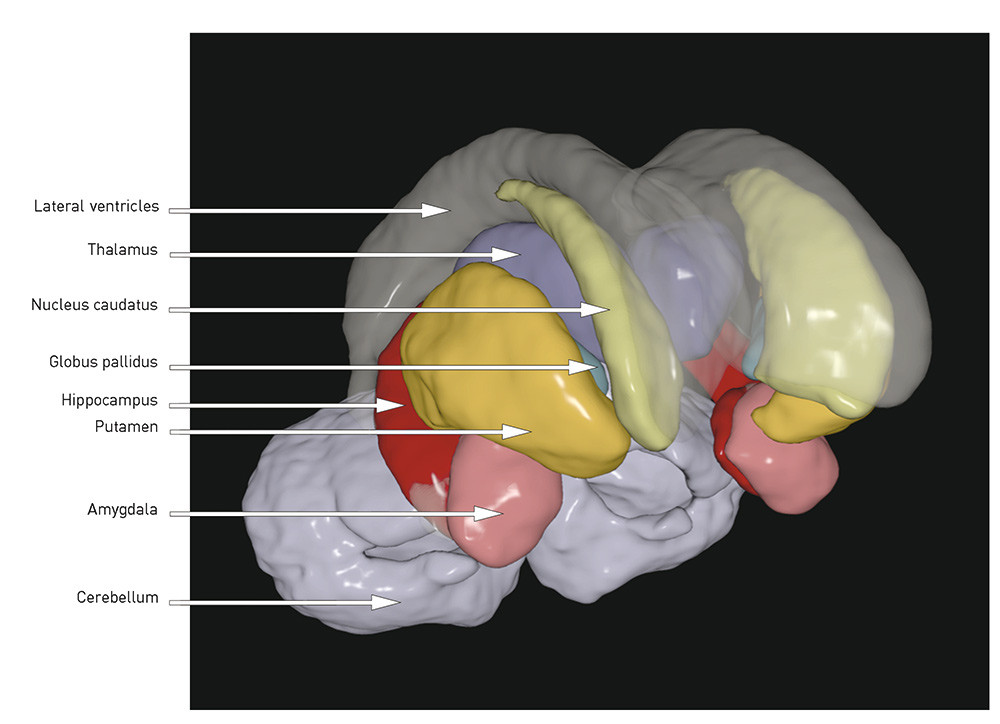

When the total volume is smaller and the ventricles enlarged, the question is whether there are certain regions or structures where the volume reduction is more pronounced. The following is a brief review of the best replicated findings (for illustration, see Figs. 1 and 2):

Fig. 2  Three-dimensional illustration of subcortical structures based on a template from the MRI post-processing tool…

Fig. 2 Three-dimensional illustration of subcortical structures based on a template from the MRI post-processing tool FreeSurfer. Illustration © Ørjan Bergmann